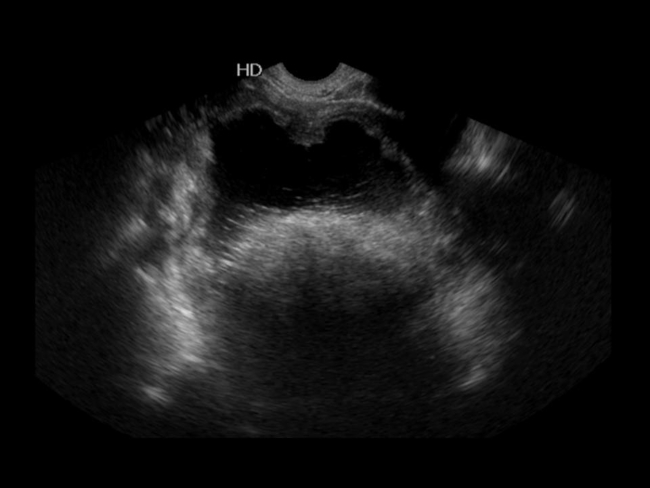

Imagen de ecografía endovaginal, donde se observa una lesión quística en área anexial derecha con el signo de la punta del iceberg que impide la visualización de estructuras por debajo del mismo.

El signo de la punta del iceberg es un hallazgo ecográfico específico de teratoma maduro, y es el resultado de la combinación de grasa, calcio y pelos cuyas interfases generan una sombra acústica posterior característica que imposibilita la visualización de estructuras por debajo de la misma, en el contexto de una lesión quística generalmente de gran tamaño. Debido a eso, es posible detectar ese signo tanto en la exploración endocavitaria como suprapúbica (►Fig. 2).2 Muchas veces, su visualización se hace dificultosa debido a que sus componentes semejan estructuras adyacentes tales como la grasa pelviana o el gas intestinal.6